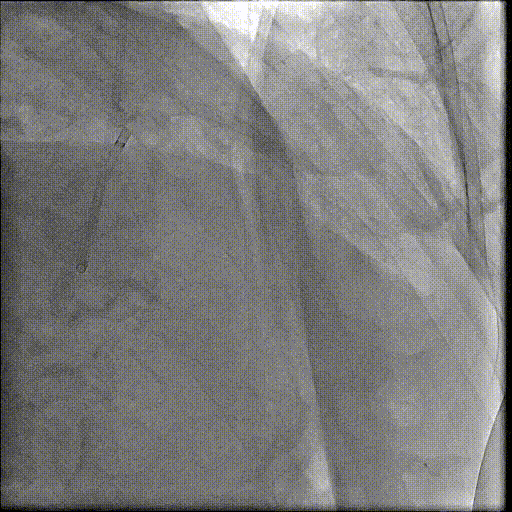

手术团队建立好通路后,沿着导丝将一个未充气的球囊送至主动脉瓣位置。球囊迅速充气膨胀,将严重钙化、几乎无法打开的「旧门」强行撑开。球囊预扩张后,真正的「主角」——压缩在输送系统中的生物瓣膜登场。团队将输送系统沿导丝送至主动脉瓣区域,在 DSA 透视和超声的双重引导下,精确调整瓣膜位置,确保新瓣膜既不会堵塞冠状动脉开口,也不会影响二尖瓣功能。当瓣膜位置确认无误后,开始缓慢释放瓣膜。

由于患者基础心功能极差,不能耐受瓣膜的多次回收释放。团队凭借丰富经验,在默契配合下仅一次就迅速将瓣膜完美植入既定位置。瓣膜释放后,跨瓣压瞬间清零。通过超声和主动脉根部造影评估手术效果:瓣膜释放位置正常,瓣膜启闭正常,无瓣周漏,术后转入 ICU 密切监测。